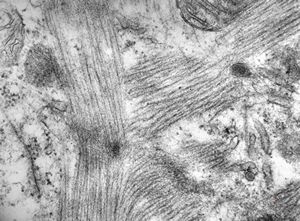

M,47y. | hypertrophic cardiomyopathy - left ventricle ( N - nucleus, T- transversally oriented, L- longitudinally oriented myofibrils )

M,47y. | hypertrophic cardiomyopathy - left ventricle-crossing of myofilaments can also be caused arteficially with bioptom